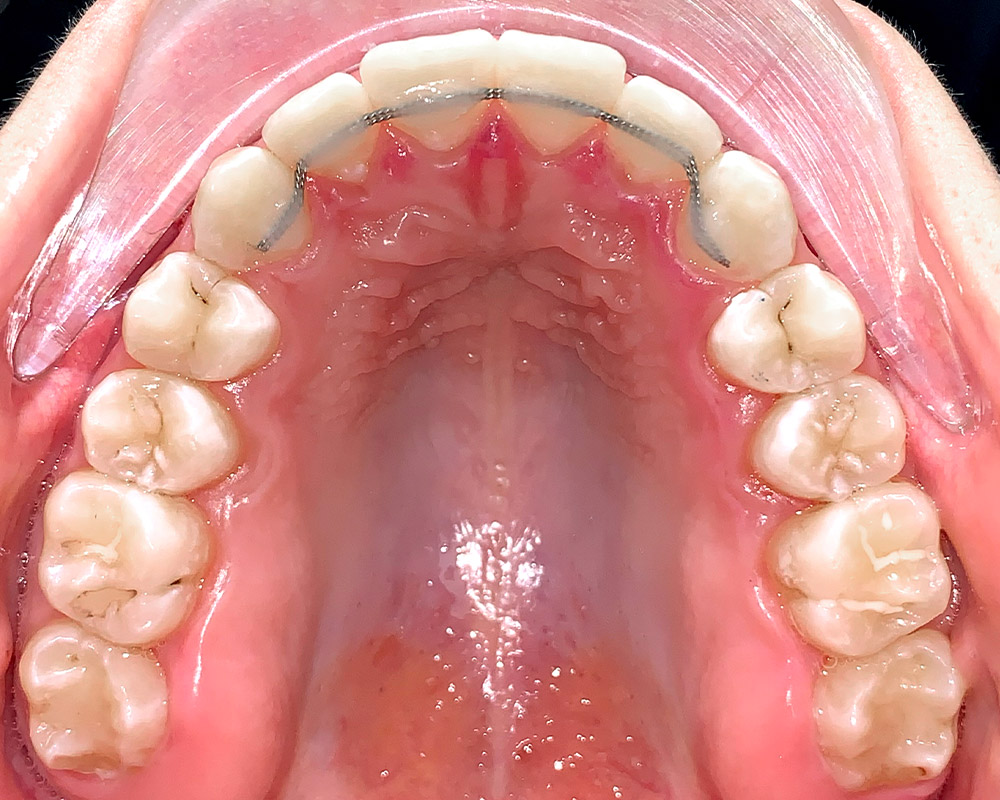

Кейс 16

Акинфиева

Количество кап ВЧ 20

Количество кап НЧ 20

ДО

ПОСЛЕ